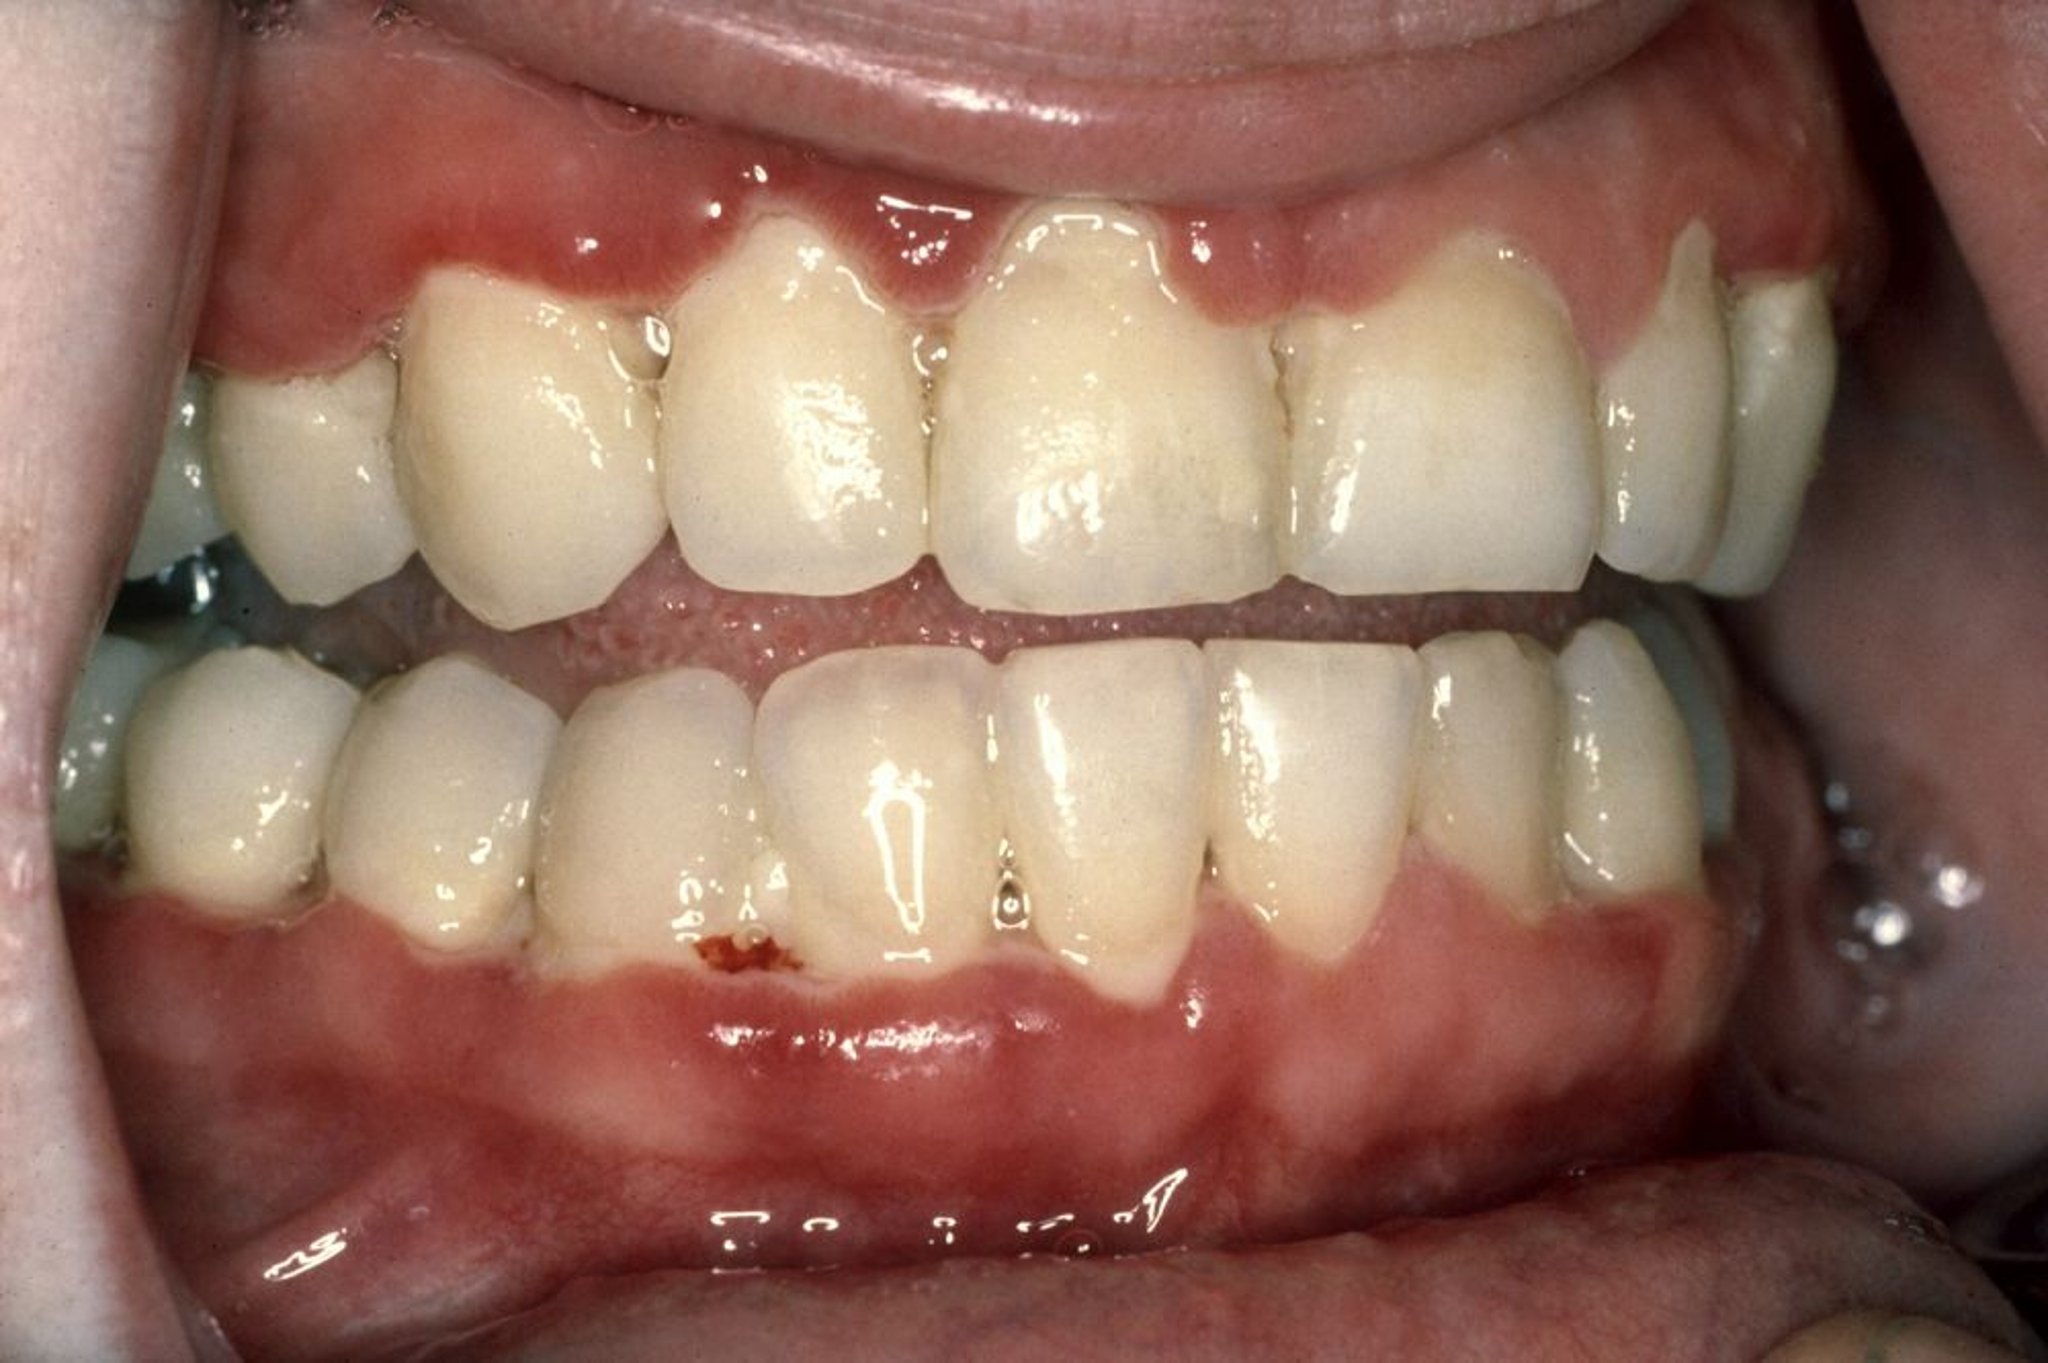

Gengivite ulcerativa necrosante aguda

A gengivite ulcerativa necrosante aguda (GUNA) caracteriza-se por gengivas doloridas que sangram com facilidade, erosão e morte do tecido gengival entre os dentes e hálito fétido. Nesta fotografia, o tecido da gengiva é vermelho vivo. Mais bem visualizada ao longo da parte frontal inferior da linha gengival, há também uma linha fina de tecido morto cinza (pseudomembrana) que sangra com facilidade.

Fotografia fornecida por cortesia de Craig Fowler, DDS